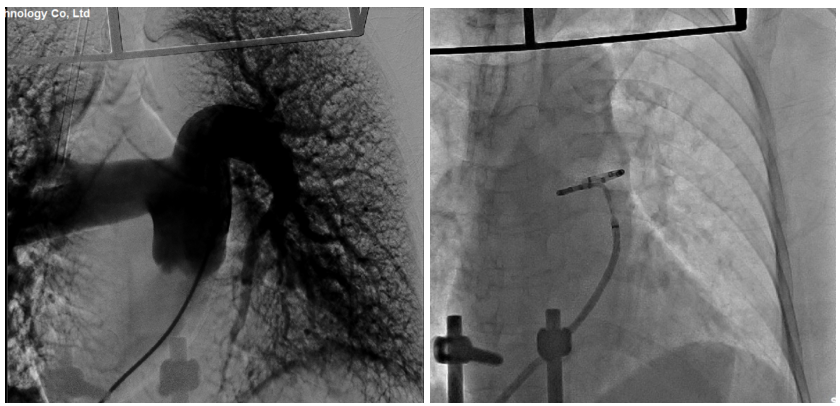

陈绍良教授团队讨论后,决定为该患者采取该领域前沿的介入治疗手段——经皮肺动脉去神经术(PADN)。在完成了充分、周全的术前准备工作后,吴皓宇副主任团队成功应用了我国原创的PADN肺动脉射频消融导管,对患者肺动脉交感神经消融靶点进行“点对点”精准消融。整个手术过程患者无明显不适,术中各监测指标平稳。右心导管检查显示,患者肺动脉收缩压由术前的91mmHg降至术后即刻的72mmHg,预期中远期肺动脉压力将进一步改善。